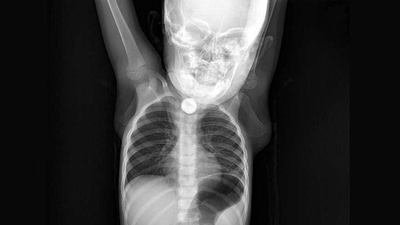

Batman'da Sevim ve İbrahim Ramazanoğlu çiftinin kusma ve ishal şikayetiyle hastaneye götürdüğü kızları Berfin'in (1,5) yassı pili yuttuğu belirlendi. Yemek borusunda ciddi yanıklar meydana gelen Berfin'in boğazının alt kısmındaki pil, operasyonla alındı.

DHA'nın haberine göre; Batman'da yaşayan Ramazanoğlu çifti, bulantı, iştahsızlık ve ishal beliren kızları Berfin'i Batman Devlet Hastanesi'ne götürdü. Doktorun muayene ettiği Berfin'in yemek borusunda cisim tespit edildi. Bunun üzerine Berfin, Elazığ Fırat Üniversitesi Hastanesi'ne sevk edildi. Burada yapılan kontrolde yassı pil yuttuğu tespit edilen Berfin, ameliyata alındı. Küçük kızın boğazının alt kısmındaki pil, başarılı operasyonla çıkarıldı. Ramazanoğlu çifti ise kızlarının, yaklaşık 3 ay önce yerde oynarken, bir cisim yuttuğunu hatırlayınca, pil yutmuş olabileceğini söyledi.

YEMEK BORUSU YANDI

Operasyonu gerçekleştiren Tıp Fakültesi Çocuk Gastroenteroloji, Hepatoloji ve Beslenme Bilim Dalı Başkanı Prof. Dr. Yaşar Doğan, "Tanı amaçlı yaptığımız endoskopi neticesinde, Berfin´in, yassı bir pil yuttuğunu belirledik. Pili çıkardıktan sonra uzun süre orada kalmasından dolayı yemek borusunda ciddi yanıklar meydana gelmişti. Hatta bu yanıklar nerdeyse nefes borusuyla birleşecek şekilde bir oluşuma gidecekti. Hastamız şu an sağlığına kavuştu. Kliniğimizde şu an oral beslenmeye geçildi. Yarın taburcu etmeyi düşünüyoruz. Yine takiplerimiz devam edecek" dedi.